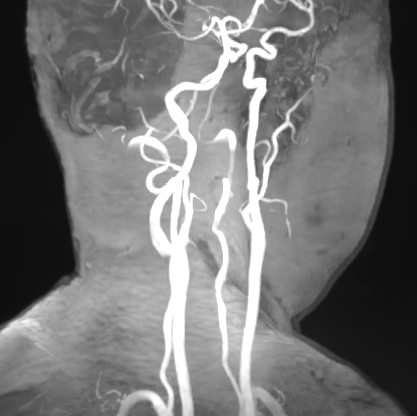

术前影像

右侧大脑中动脉瘤,右侧椎动脉V2-V3粗细不均伴局部扩张